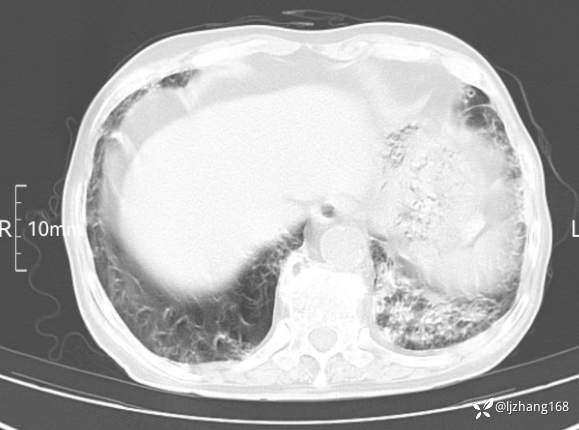

辅助检查:胸部CT:双肺肺气肿,间质性病变,血气分析:PH 7.413, PCO2 29.2mmHg, PO2,81.8mmHg,乳酸 3.3mmol/1,剩余碱-4.0mmol/1,HC03 18.8mmol/1。全血超敏C反应蛋白:超敏C反应蛋白 135.60 mg/L、 白细胞 14x19^9/L,中性粒细胞11.6x10^9/L。